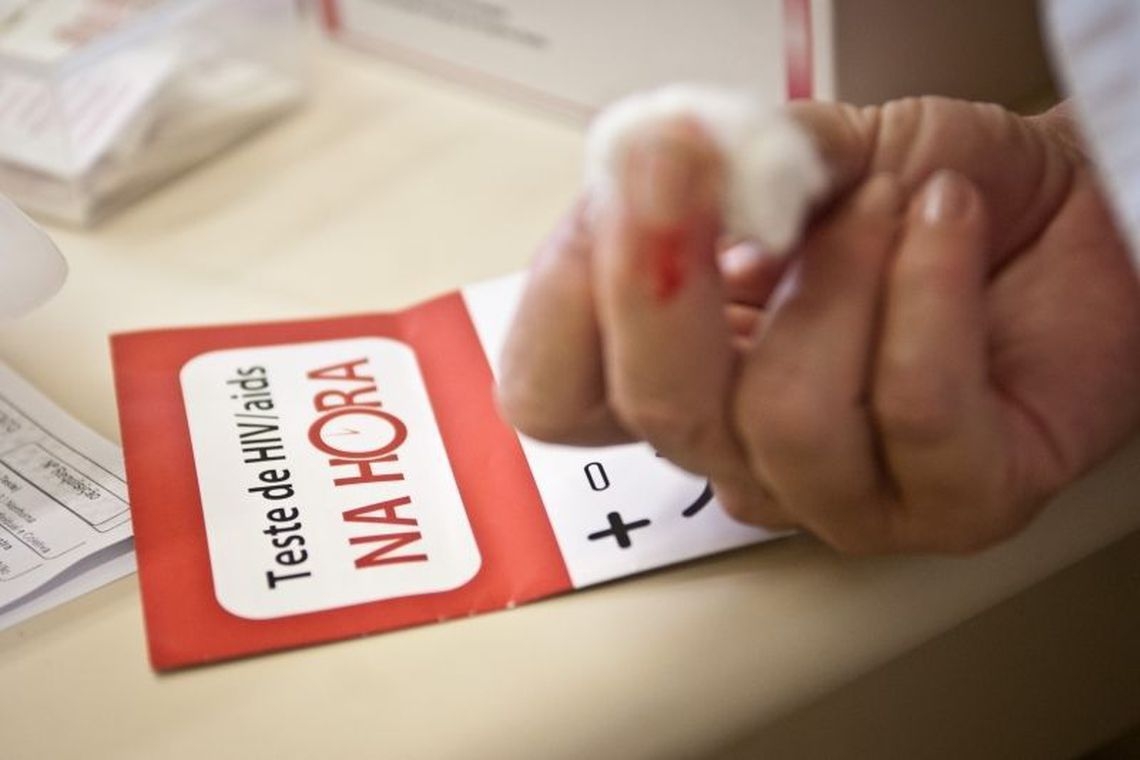

Estudo relata caso de mulher curada de HIV sem tratamento médico

Com isso, eles concluíram que a mulher pode ter alcançado naturalmente a cura esterilizante, quando não há vírus circulante e a eliminação dos reservatórios virais acontece mesmo sem a intervenção de terapias antirretrovirais.